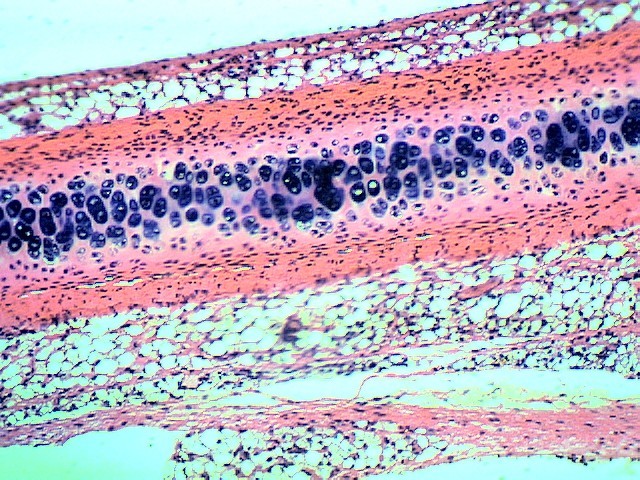

Кровеносные сосуды - 3 шт.